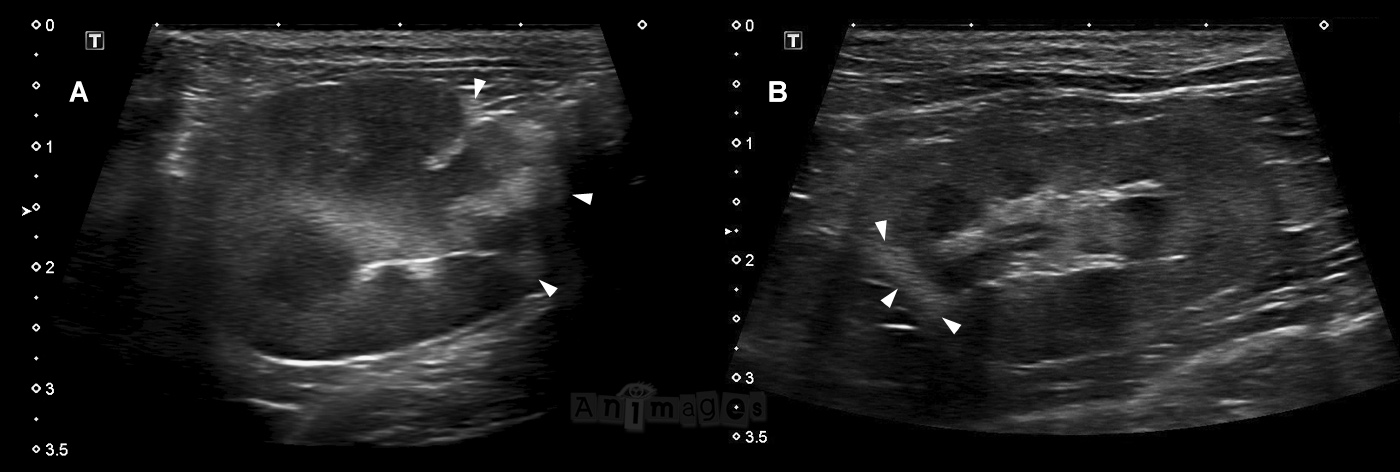

Les images ci-haut provenant de deux chats différents illustrent bien l’apparence classique de ces infarcti. Notez l’atrophie consécutive de la section hyperéchogène du cortex atteint, déformant le contour du rein. Le clip ci-bas permet d’apprécier le rein en A de façon dynamique. Ce chat ne présentait pas de souffle cardiaque au moment de l’examen, mais une échographie cardiaque n’a pas été réalisée pour exclure plus définitivement une cardiomyopathie sous-jacente. Le chat en B avait quant à lui une cardiomyopathie hypertrophique confirmée.